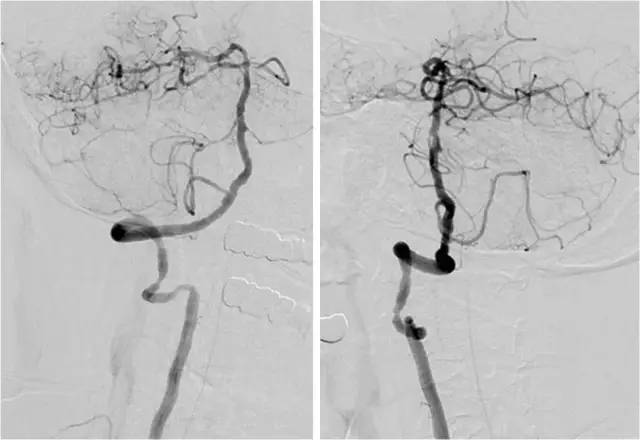

DSA:右大脑中动脉闭塞。左大脑前动脉A1段缺如。左胚胎型大脑后动脉。右椎动脉优势,右椎动脉V1及V4段重度串联狭窄。左椎动脉起始段狭窄,V4段闭塞。患者造影过程中存在一定程度不自主运动,故图像显影较差(图3-6)。

图3

图4

图5

图6